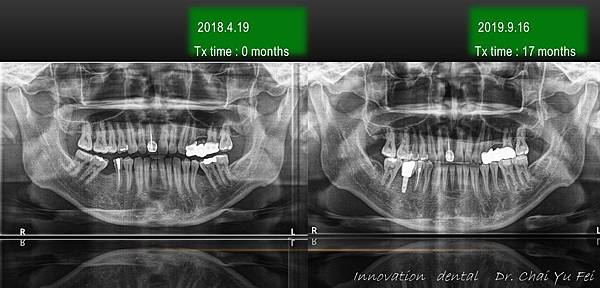

成人矯正|想重建全口咬合?矯正、植牙、牙橋合併案例-陳先生

[ 矯正醫師 ] : 展心牙醫  翟聿飛 醫師 [ 植牙醫師 ] : 展心牙醫  王鵬懿 醫師 [ 治療方式 ] : 利用迷你骨釘 , 將傾倒的臼齒扶正,製造空 …